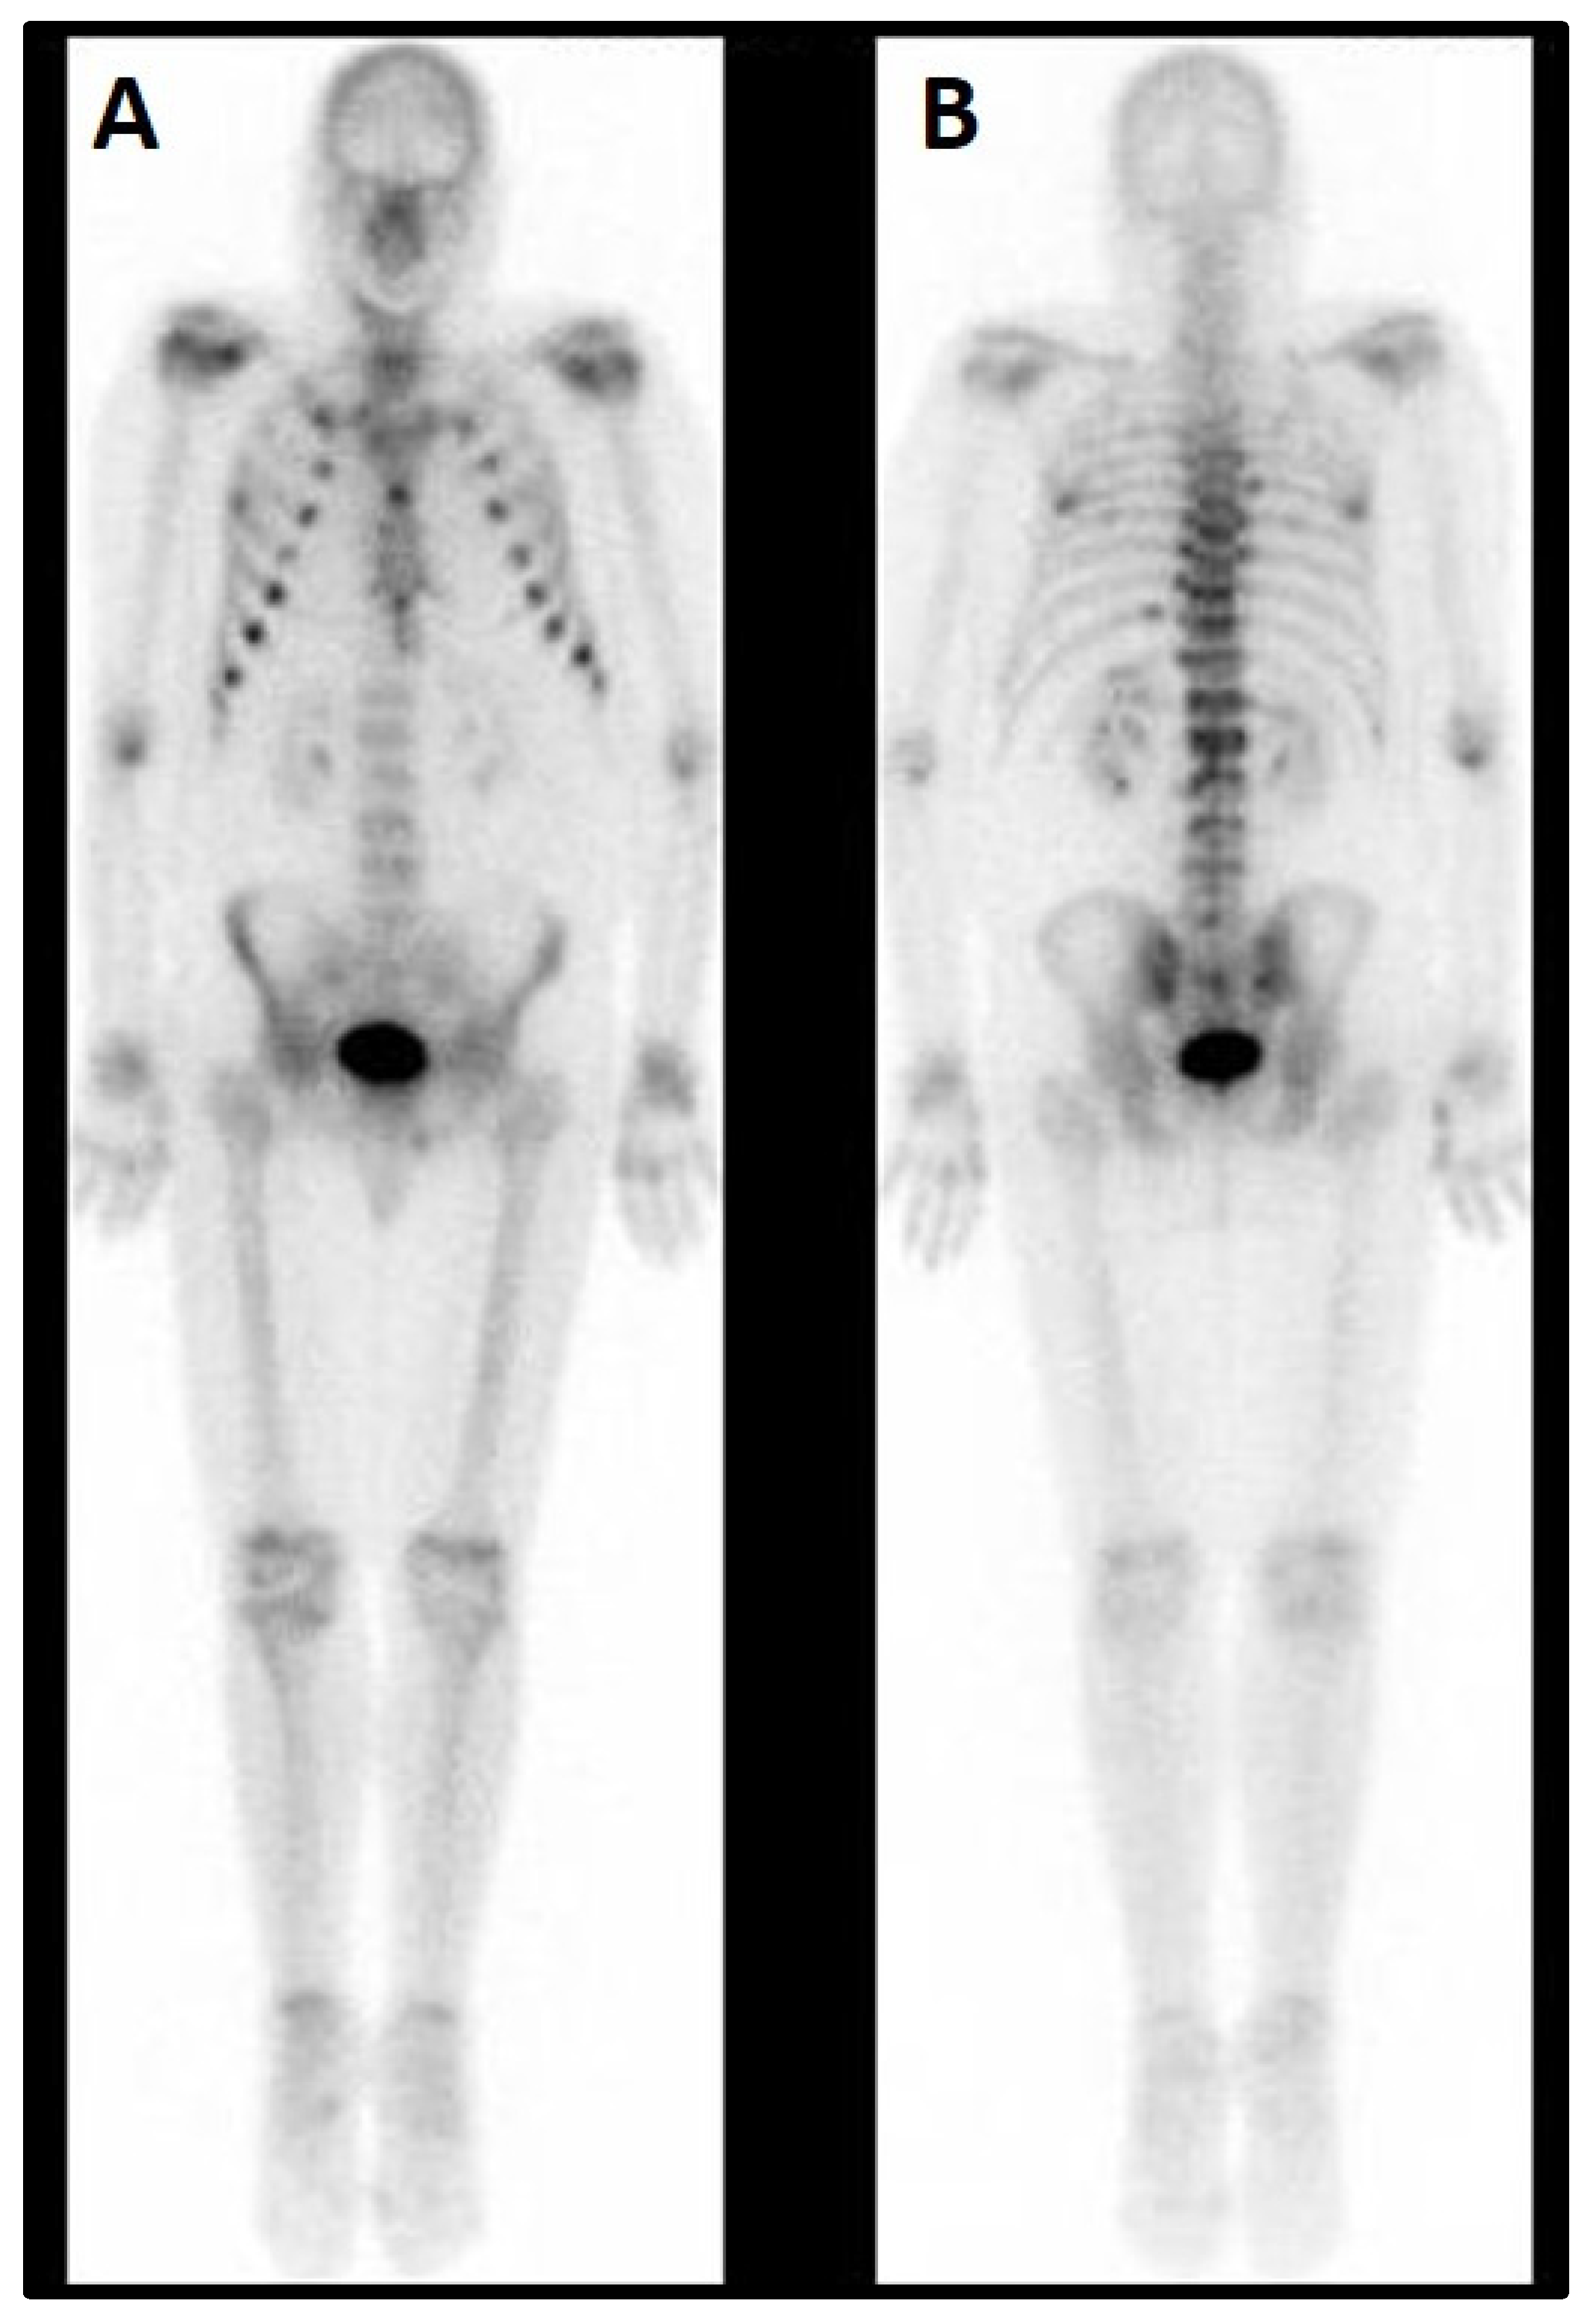

Although the DEXA cannot be considered a radiological examination/imaging diagnostic tool, the left femoral neck appeared much shorter, compatible with a closed fracture. Moreover, and more interestingly, at the T12/L1 spine level, an hyperdense area was clearly detectable. This was further investigated by the mean of Global PET Ga68, that showed hypercaptation at the expansive formation in T12-L1 with narrowing of the vertebral canal and bone lysis at the L1 vertebral body and transverse and spinous processes levels. Moreover, the exam denoted an increased uptake in a small encephalic area of the frontal cortex (Figure 4A,B).

Figure 4. Global PET (Ga68-DOTATOC). (A) Spine. The white arrow indicates hypercaptation at T12/L1. (B) Skull. The white arrow indicates a focal area of increased uptake (max. axial diameter 13 mm).